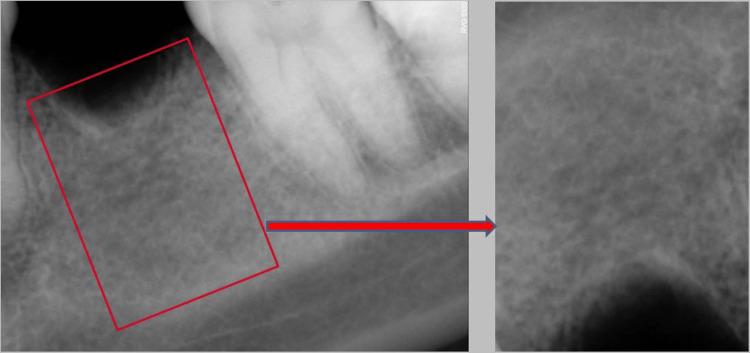

Background Pre-prosthetic implant radiographic imaging helps in the quantitative and qualitative analysis of the bone structure and also enables the evaluation of the relationship between critical structures and potential implant sites. Purpose The aim of the study was to define the reliability of utilizing the analysis of textures from the periapical radiographic images obtained through Radiovisiography (RVG) in order to better plan for dental implantations. Methods A cross-sectional study was conducted using 50 intraoral periapical radiographs which were obtained through RVG performed prior to the placement of implants. The radiographs were segregated based on anatomical locations i.e. 12 for the anterior maxilla, nine for the posterior maxilla, seven for the anterior mandible, and 22 for the posterior mandible. Each of the radiographs was visually assessed by four experienced examiners, namely a Prosthodontist E1, Periodontist E2, Oral surgeon E3, and Oral radiologist E4, which was then compared to an experienced operator's tactile perception during a pilot drill for implant placement. As a reference, the Lekholm and Zarb classification was provided to all the examiners for them to qualitatively assess the bone structure in the radiographs. Results The examiners' results were correlated with the assessment provided by the experienced operator. E1 and E4 successfully assessed 42% of the radiographs while E2 had the least success with only 26%. Of the 12 anterior maxillary radiographs, only eight were accurately assessed by E1. With respect to the posterior maxilla, all examiners correctly assessed four radiographs each. Of the seven anterior mandibular radiographs, except for E2, the rest correctly assessed three radiographs each. Of the 22 posterior mandibular radiographs, only nine were accurately assessed by E4. Conclusion Intraoral periapical radiographs obtained through RVG did not meet the desired parameters for assessing the bone quality during the planning stage for implants.

修复前种植体放射影像学成像有助于对骨结构进行定量和定性分析,还能评估关键结构与潜在种植部位之间的关系。目的:本研究旨在确定利用通过放射成像(RVG)获得的根尖片纹理分析来更好地规划牙种植的可靠性。方法:进行了一项横断面研究,使用50张在种植体植入前通过RVG获得的口腔内根尖片。这些根尖片根据解剖位置进行分类,即上颌前部12张,上颌后部9张,下颌前部7张,下颌后部22张。每张根尖片由四位经验丰富的检查者进行视觉评估,分别是修复医生E1、牙周病医生E2、口腔外科医生E3和口腔放射科医生E4,然后将其与经验丰富的操作人员在种植体植入导向钻操作过程中的触觉感知进行比较。作为参考,向所有检查者提供了Lekholm和Zarb分类,以便他们对根尖片中的骨结构进行定性评估。结果:检查者的结果与经验丰富的操作人员提供的评估相关。E1和E4成功评估了42%的根尖片,而E2的成功率最低,仅为26%。在上颌前部的12张根尖片中,E1仅准确评估了8张。关于上颌后部,所有检查者各自正确评估了4张根尖片。在下颌前部的7张根尖片中,除E2外,其余检查者各自正确评估了3张根尖片。在下颌后部的22张根尖片中,E4仅准确评估了9张。结论:通过RVG获得的口腔内根尖片在种植体规划阶段评估骨质量时未达到预期参数。